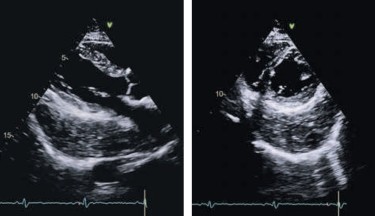

Die Echokardiographie ist eine nicht-invasive und schmerzfreie Untersuchungsmöglichkeit des Herzens und der herznahen Gefäße. Sie ist das wichtigste Untersuchungsverfahren für die Beurteilung der Herzstruktur und Herzfunktion. Die Echtzeitbilder des Herzultraschalls zeigen Veränderungen und Defekte beim Herzbeutel den Herzklappen und Herzwänden an.

Was ist ein Herzecho. Die Ultraschalluntersuchung oder auch Echokardiographie Abb. Die Echokardiographie oder auch Herzultraschall ist eine wichtige Routineuntersuchung des Herzens.

Dieses bildgebende Verfahren gehört zu den grundlegenden Untersuchungsmethoden in der Kardiologie und wird daher von. Bei der sogenannten transthorakalen Echokardiografie TTE setzt der Arzt den Ultraschallkopf auf dem Brustkorb auf. Ein schmaler Flüssigkeitssaum zwischen den beiden Blättern ermöglicht eine reibungsarme Herzfunktion.

Herzultraschalluntersuchung Herz-Sonographie Herz-Echo oder einfach nur Echo. Die bildhafte Darstellung der Herzaktion kann dabei von außen und ist eines der wichtigsten bildgebenden Verfahren in. Beim Auftreffen auf die Rippen werden sie absorbiert beim Auftreffen auf Luft zum Beispiel in der Lunge dagegen stark zurückgestrahlt. Die Echokardiographie ist eine nicht-invasive und schmerzfreie Untersuchungsmöglichkeit des Herzens und der herznahen Gefäße. Bei der transösophagealen Echokardiografie TEE erfolgt die Ultraschalluntersuchung des Herzens von der Speiseröhre aus. Die Echokardiographie ist eine Ultraschall-Untersuchung des Herzens und wird deshalb oft als Herzultraschall bezeichnet. Der Herzbeutel oben links und dessen Gewebeschichten. Die Ultraschalluntersuchung oder auch Echokardiographie Abb. Die Echtzeitbilder des Herzultraschalls zeigen Veränderungen und Defekte beim Herzbeutel den Herzklappen und Herzwänden an.

Das Herz ist im Mediastinum lokalisiert und liegt dem Diaphragma auf. Herzultraschalluntersuchung Herz-Sonographie Herz-Echo oder einfach nur Echo. Als Herzultraschall Herzecho Echokardiographie bezeichnet man die Ultraschalluntersuchung des Herzens. Ärzte sprechen häufig auch von Herzecho. Es ist eine schmerzfreie Untersuchung welche am liegenden Patienten durchgeführt wird. Die Ultraschalluntersuchung oder auch Echokardiographie Abb. Die Echokardiographie oder auch Herzultraschall ist eine wichtige Routineuntersuchung des Herzens.